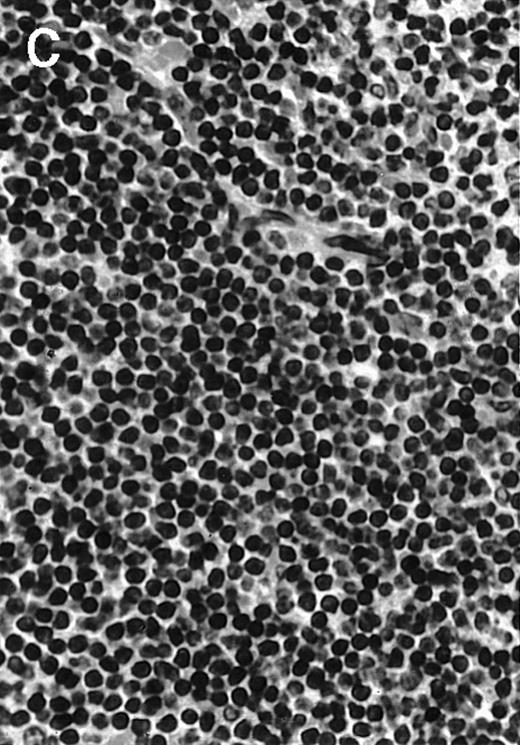

To explore the mechanisms of the protection from BCL growth, histologic analysis was performed on tumor tissue from mice treated with ST40L, ST, or PBS alone. In the mice treated with PBS alone, no cellular infiltrate expressing FasL was observed in the surrounding tissues and inside the BCL region (Figure 4A and D). In contrast, infiltrating lymphocytes expressing FasL were observed around the vessels and also scattered in the smaller tumor tissues in the mice treated with ST (Figure 4B and E). Small hard nodules (2-5 mm in diameter) were observed at the SC injection sites of the long-term survival mice that had been treated with ST40L. On histologic analysis, these small nodules were confirmed to be the result of an accumulation of lymphocytes, and not BCL cells (Figure 4C). These lymphocytes were also found to be strongly positive for FasL expression (Figure 4F). On the other hand, lymphocytes infiltrating in the nodules were stained by either CD4+ Ab or CD8+ Ab, but the ratio of CD4+ and CD8+ cells was not 1-sided (data not shown).

Histologic analysis of A20 tumors excised 21 days postchallenge from BALB/c mice immunized with ST40L.

(A) HE stain of a BCL region in a mouse treated with PBS alone. (B) HE stain of a smaller BCL region in a mouse treated with ST. (C) HE stain of a small hard nodule at the SC injection site in a mouse treated with ST40L. (D) Fas ligand staining of a BCL region in a mouse treated with PBS alone. (E) Fas ligand staining of a BCL region in a mouse treated with ST. (F) Fas ligand staining of a small hard nodule at the SC injection site in a mouse treated with ST40L. Original magnifications are ×400.